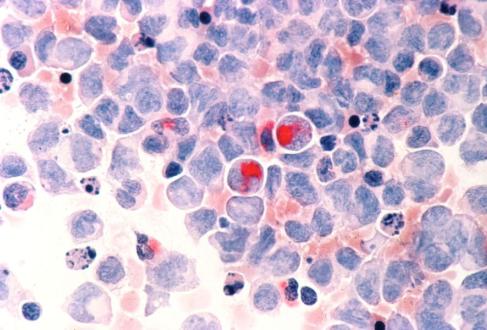

Cracking cancer’s code: New research identifies novel drug target for acute myeloid leukemia treatment

Despite advances in cancer treatment in recent years, five-year survival rates for acute myeloid leukemia (AML) remain low at just 30% on average, according to the National Cancer Institute. Factors in the development of AML are diverse with many different drivers. A longtime goal for scientists in this field is finding a single drug that can treat all types of AML.